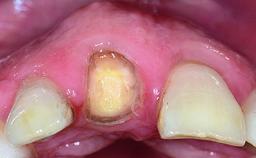

Replacement of a Perforated Upper Left Central Incisor: Early Placement of an RC Bone Level Implant

A 28-year-old patient presented at her general dentist’s office and complained about the appearance of her tooth 21. The patient had a history of trauma to this tooth. Endodontic treatment had been performed in the past and a crown placed on the tooth. A procedure to replace the old crown was performed by her dentist; however, a perforation on the middle third of the root occurred, and extraction of tooth 21 was suggested. Upon clinical and radiographic examination of the patient, who had been referred to us, replacement of tooth 21 by a dental implant appeared to be indicated.